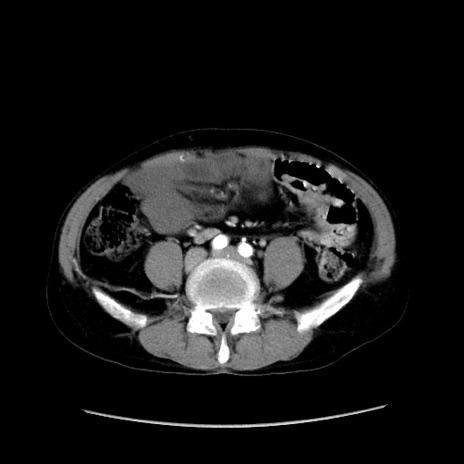

症例37(横断像)

【症例】40歳代 男性

【主訴】腹痛

【現病歴】4時間ほど前に電車に乗車中に臍部上より腹痛出現。徐々に増悪し起立困難となり、救急外来受診。生ものは数日食べていない。今朝お雑煮を食べた。

【身体所見】BT 36.8℃、BP 117/84mmHg、HR 91/min、SpO2 97%、苦悶様、腹部:臍上部広範囲圧痛あり、反跳痛±

【データ】WBC 8100、CRP 0.03